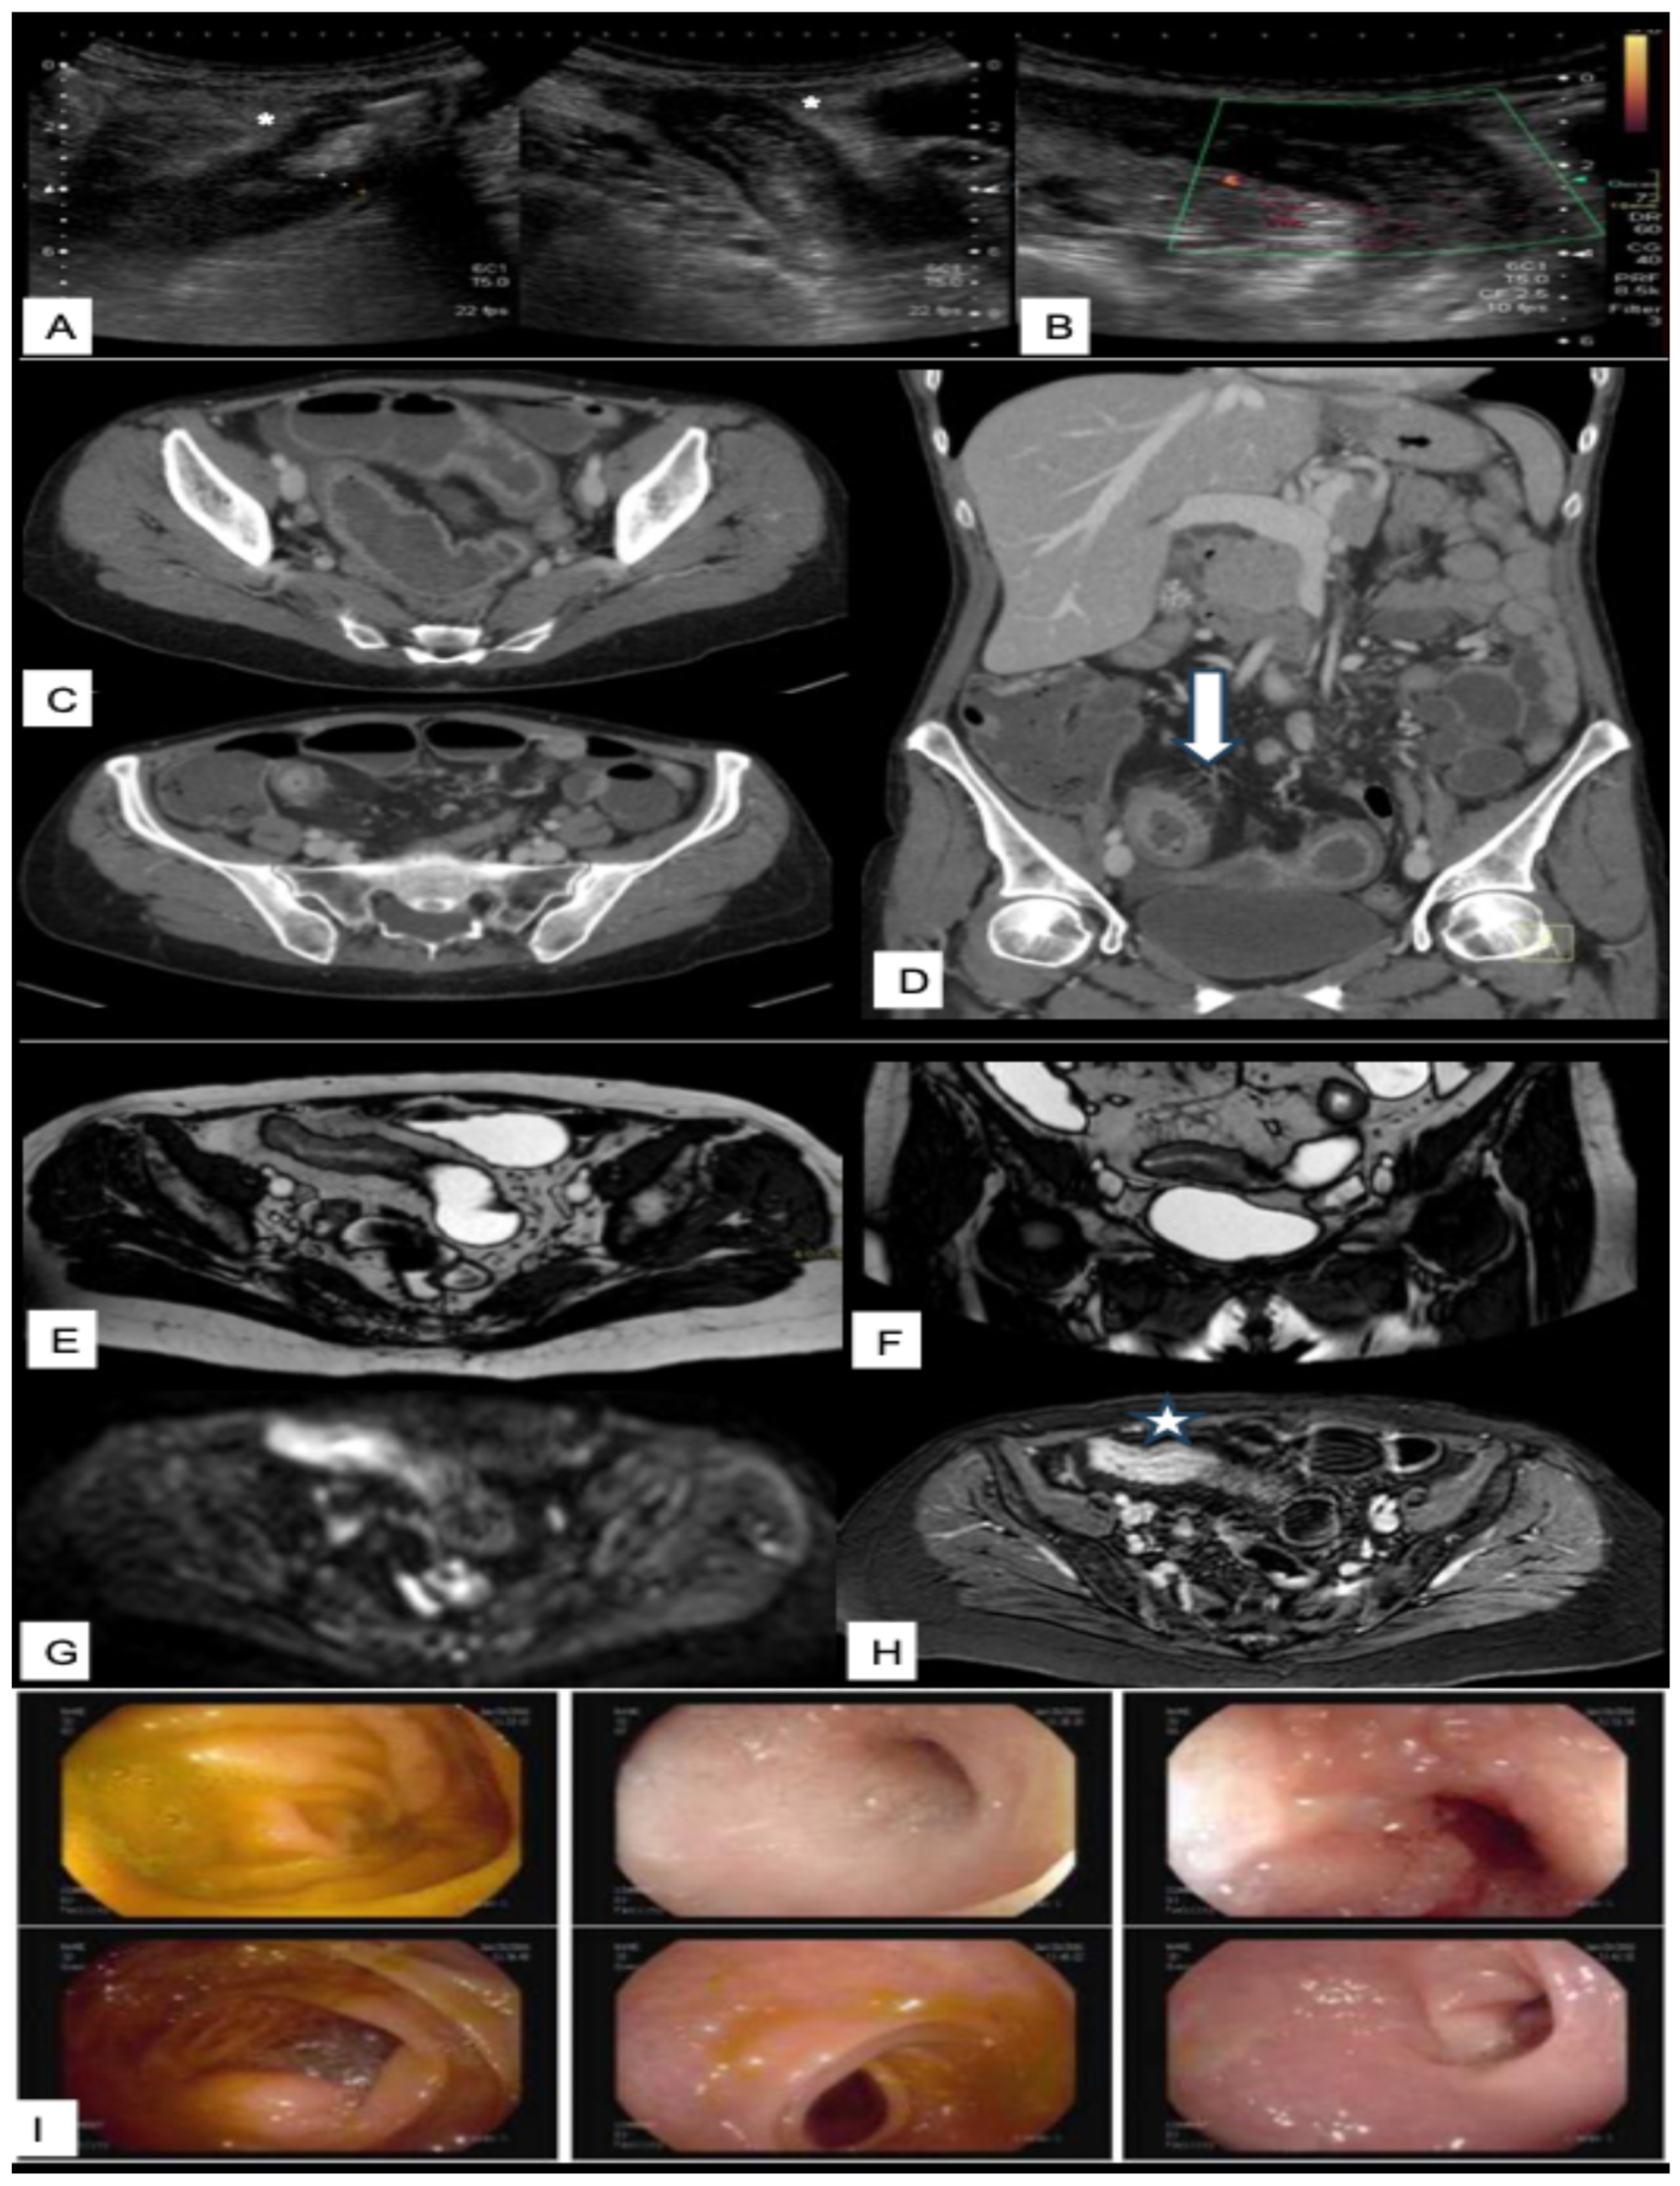

Intestinal Ultrasounds Imaging Findings and Scoring Systems

3.3. CT and CT Enterography

3.4. Magnetic Resonance Imaging

3.4.1. MRI Techniques and Sequences in IBD

3.4.2. Typical MRI Findings in Crohn’s Disease

3.4.3. Typical MRI Findings in Ulcerative and Indeterminate Colitis

3.4.4. Diagnostic Performance of MRI vs. Endoscopy and Histology

3.4.5. MRI-Based Scoring Systems in IBD

3.4.6. MRI in Assessing Treatment Response